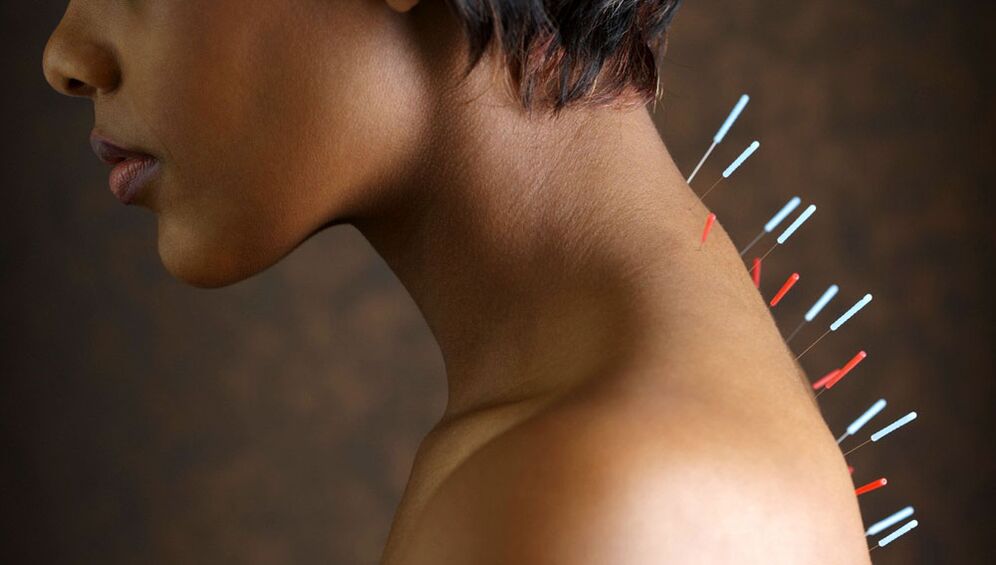

Acupuncture

Ang acupuncture ay nag -aambag sa pagpapalabas ng cortisol sa dugo. Ang hormone na ito ay may binibigkas na anti -inflammatory effect.

Ang acupuncture ay isinasagawa sa pamamagitan ng pagkakalantad sa mga puntos na malapit sa panloob na gilid ng scapula. Ang mga karayom ay ipinakilala sa lalim ng 1 - 2 cm at naiwan para sa pagkakalantad sa 10 - 30 minuto.